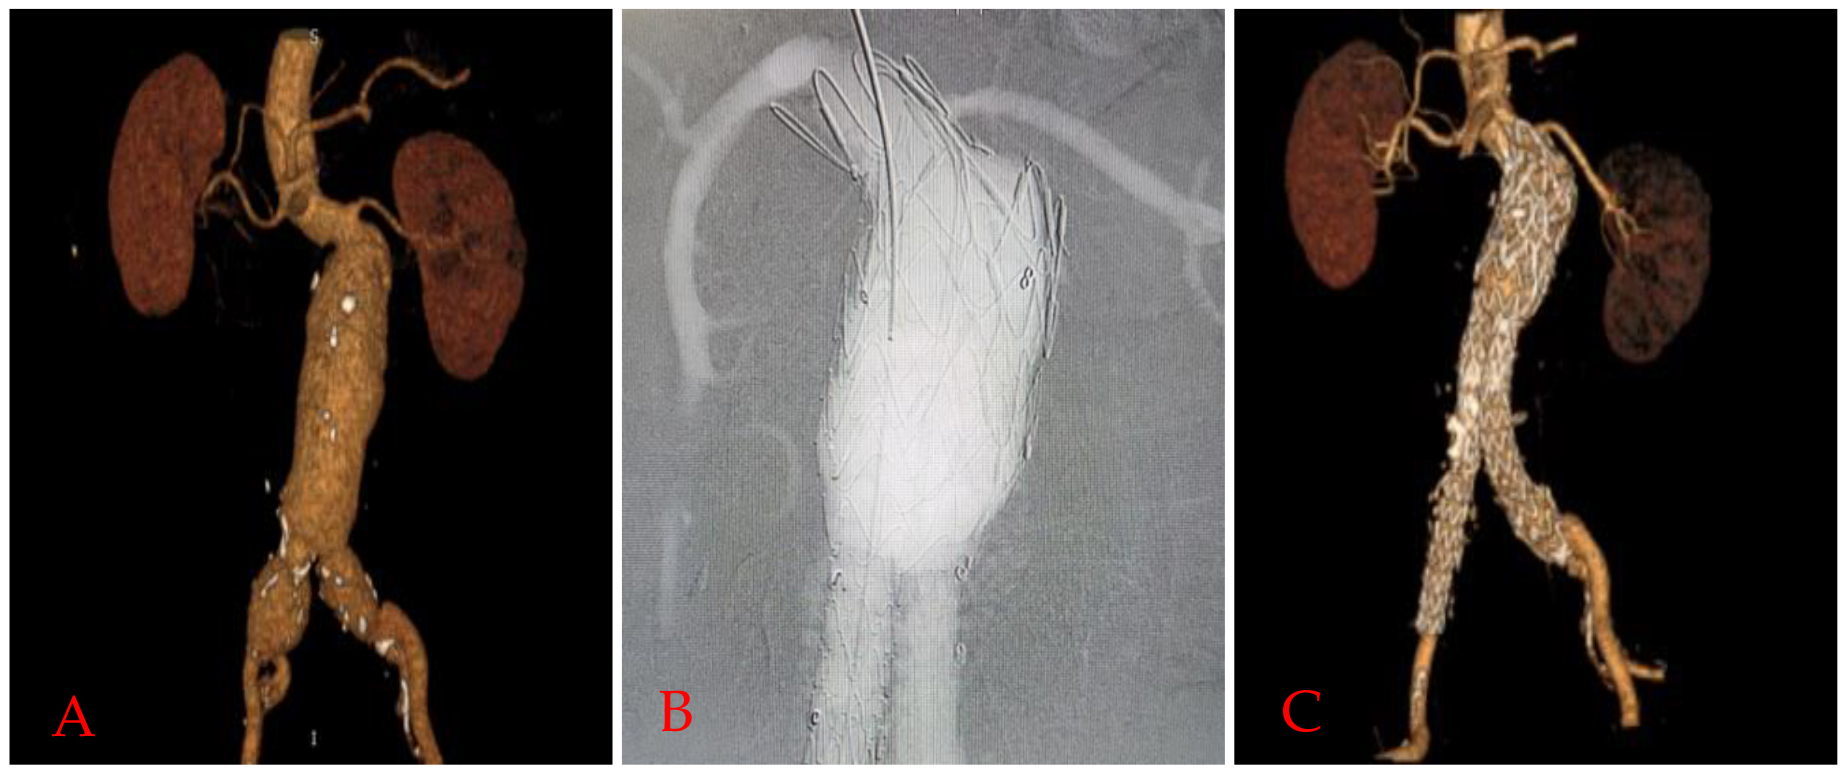

Fig. 1.Funnel EVAR application in a patient with hostile neck.

Preoperative 3D reconstruction image of computed tomographic angiography scan

(A), completion angiography image (B), and 24. Month computed tomographic

angiography (CTA) controls (C) of a